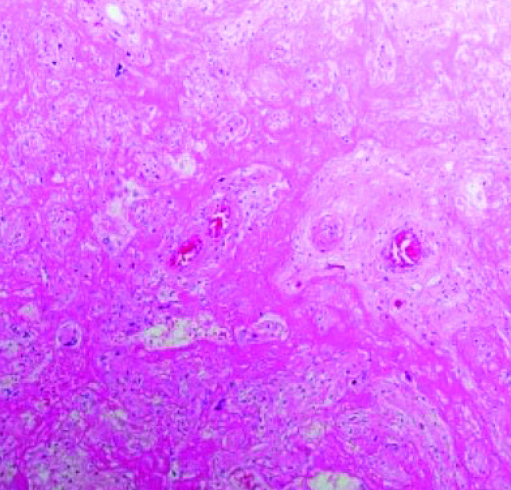

Массивное выпадение фибрина (см. рис. 3) — очень заметный и яркий признак. Иногда ворсины настолько замурованы выпавшим фибрином, что их трудно найти и рассмотреть, циркуляция материнской крови нарушена. Газообмен в плаценте значительно снижается или вовсе прекращается, что ведет к гипоксии и гибели плода.

Сканируя гистологические препараты на малом увеличении, мы видели крупные участки тромбоза с массивным выпадением фибрина в межворсинчатом пространстве. На большом увеличении в периферии участков тромбоза наблюдается воспалительная инфильтрация в ворсинах и межворсинчатом пространстве. Можно рассмотреть, как фибрин буквально заклеивает собой ворсины.

В основном это свежий фибрин, хотя наблюдаются и участки более зрелого фибрина. То есть на морфологическом уровне мы предполагаем, что поражение плаценты происходит достаточно быстро и ведет к гибели плода. Все это подтверждается и клиническими данными.